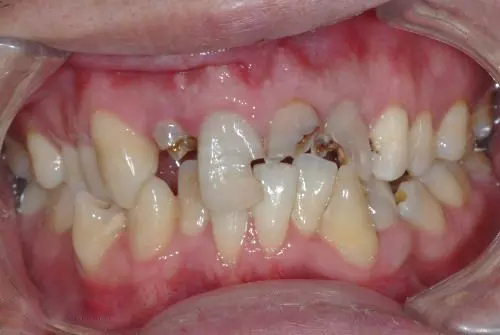

牙体缺损是指牙体硬组织不同程度的质地和生理解剖外形的损坏或异常。当牙体硬组织部分缺损且较大时称为残冠,当牙体硬组织全部缺失或者接近全部缺失称为残根。

什么样的残根、残冠需要拔除?

1、残根、残冠大面积龋坏、根尖周病无法治愈的患牙;

2、晚期牙周病、牙槽骨严重吸收、松动严重的残根、残冠;

3、残留的残根、残冠引起骨髓炎、囊肿;

4、残根、残冠纵裂、根裂、折断或已有根内外吸收;

6、肿瘤或肿块波及邻牙或恶性肿瘤放疗前要求拔除的残根、残冠;

6、疑为风湿病、肾炎、视神经炎等疾病的病灶残根以及引起骨髓炎的残根、残冠;

7、智齿的残根、残冠;

8、乳牙的残根、残冠。